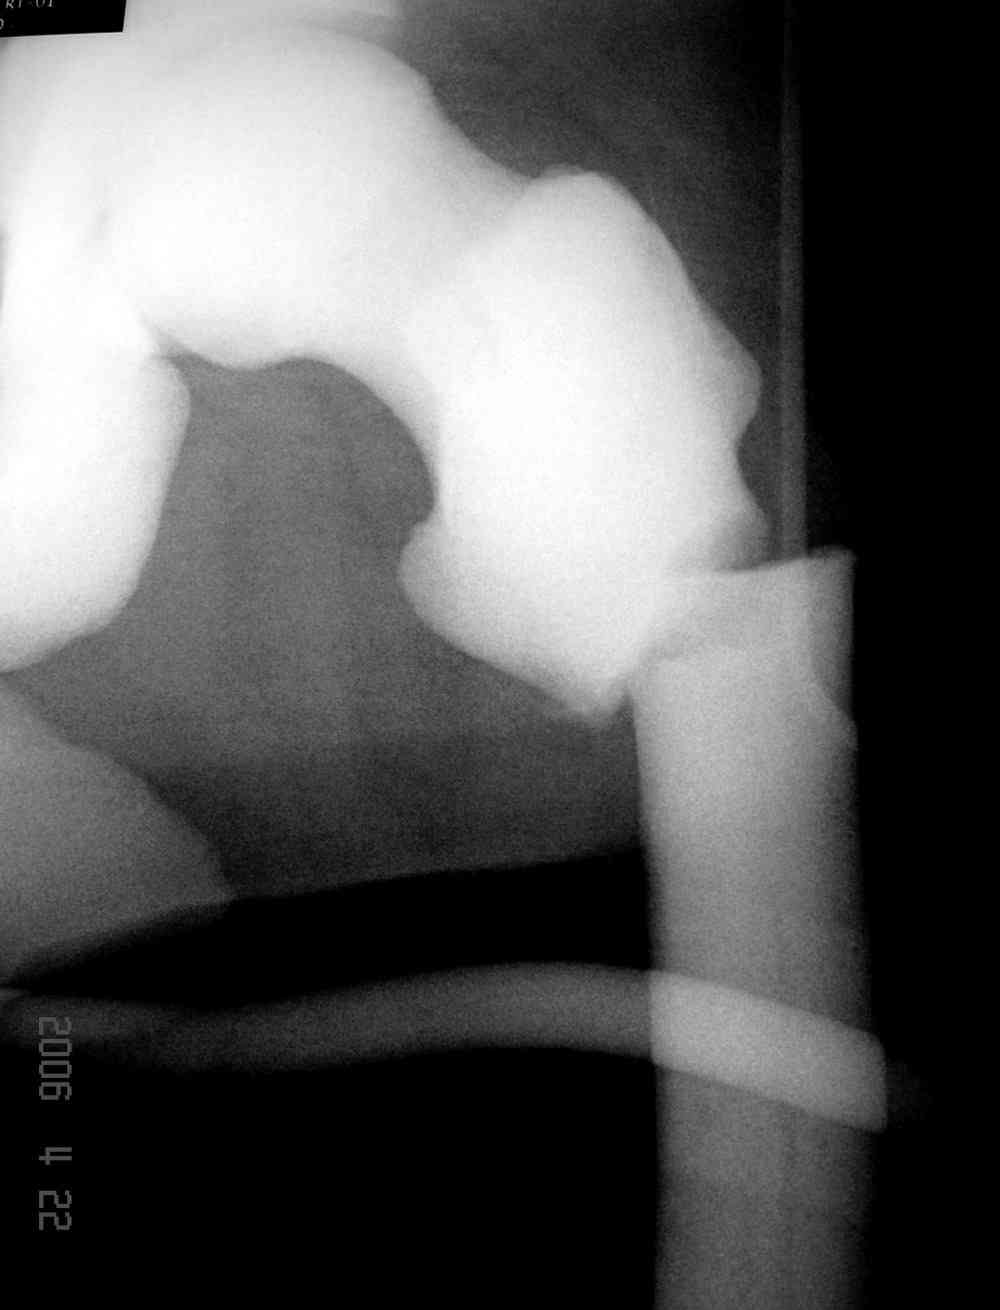

“При лечении переломов у больных с остеопетрозом (в прошлом году был случай) необходимо быть готовым к длительным операциям из-за трудности

обработки традиционными методами "мраморной" кости, иметь в наличие достаточное количество свежих острых инстументов и персонала при необходимости замены (были случаи отстрочки операции на следующий день из-за физической усталости персонала), и надо избежать особо трудоемких операции как интрамедуллярное сверление”.

слайды из прошлегодного случая.